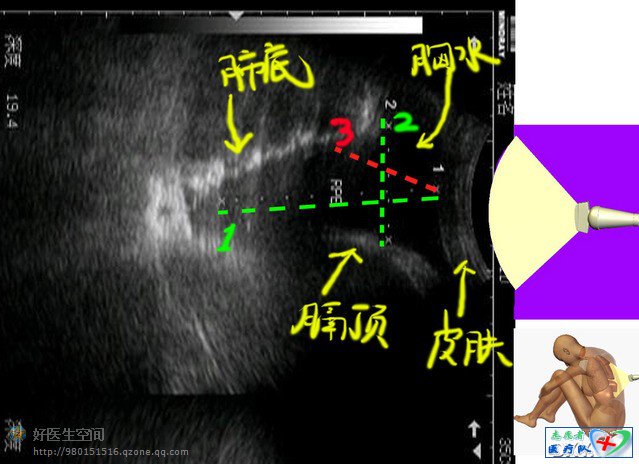

这里面就有安全隐患了,我们先来分析一下这个报告,我们把这个图转90度这样就符合我们的审美要求了,首先我们分清哪里是皮肤,哪里是胸水,哪里是被压迫肺下缘,哪里是膈肌上缘,注意我旁边付了一张小图,这样亲们就可以理解了,还有不明白的吗?不明白请举手

有些B超医生把前后径定位在绿线1出,这个很危险,不当无法估计胸水量,而且胸水少时这个前后径很细,就是一条小缝,歪一点就扎到肺了,临床医生以为胸水很多,深度10cm呢,一针下去,到肺了

绿线2是上下径,这个上下径应该定在哪个位置也是靠感觉,

现在很多B超医生把前后径定在红线3处,这样比较合适,但斜到什么水平也是跟着感觉走